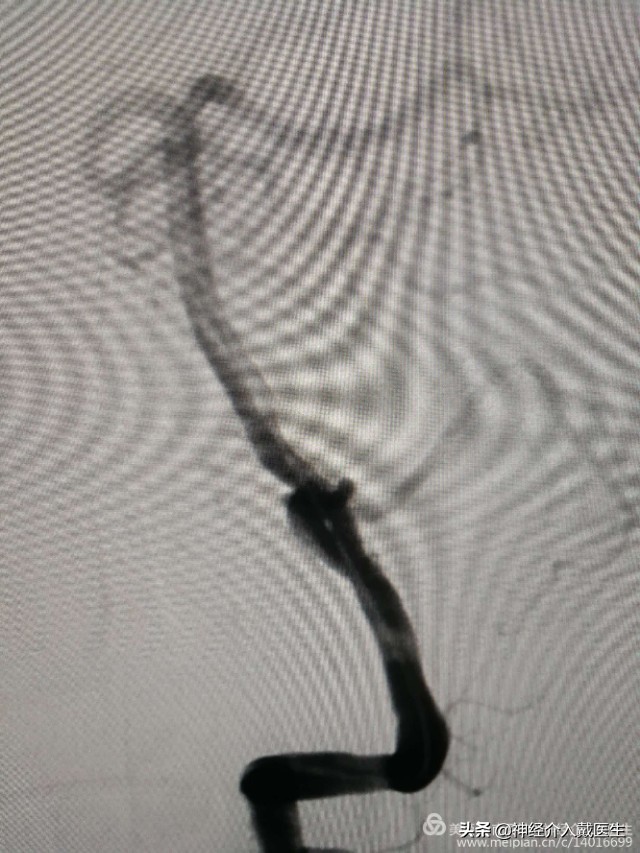

复查椎动脉正位,动脉瘤不显影,载瘤动脉及右侧小脑后下动脉通畅。

复查椎动脉侧位,动脉瘤不显影,载瘤动脉及右侧小脑后下动脉通畅。遂结束手术。